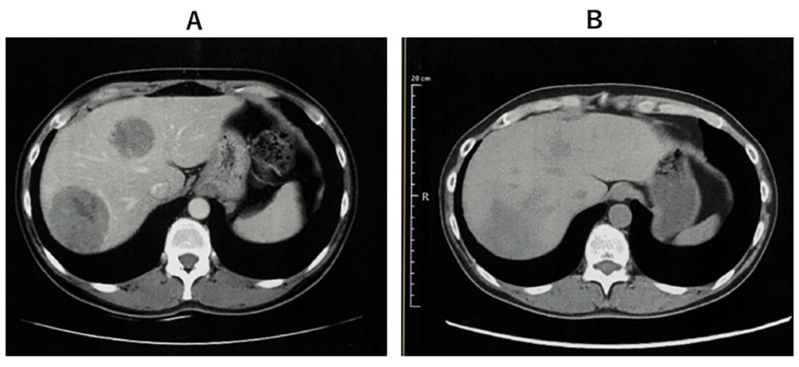

案例2:难治性宫颈癌转移灶消失,免疫功能恢复

小细胞未分化宫颈癌进展快、易耐药,预后极差。《Cureus》报道了一则突破性案例:一位 50 多岁的患者术后出现肝、淋巴结多处转移,化疗失败后,采用 WT1-DC 疫苗联合放疗: 1、第 67 天(注射第 5 剂疫苗后),CT 显示肝转移灶完全消失; 2、免疫指标(中性粒细胞 / 淋巴细胞比值等)恢复正常,原本因化疗受损的免疫功能显著改善。 案例3:胰腺癌患者中位生存期突破3年,7人成功手术 胰腺导管腺癌被称为 “癌王”,对放化疗天然耐药。《癌症免疫治疗杂志》的一项研究带来了新希望:10 例不可切除的胰腺导管腺癌患者(6 例 III 期局部晚期、3 例 IV 期转移性、1 例术后复发)采用 WT1-DC 疫苗联合化疗后: 1、所有患者肿瘤负荷下降,7人达到部分缓解,3人长期稳定; 2、9例患者中位无进展生存期 2.23 年,中位总生存期更是突破 3.52 年,远超传统治疗的预期。 3、 7 例成功接受了转化手术,其中 6 例实现 R0 切除(肿瘤完全切除,无残留),1 例为 R1 切除(镜下有残留)。 案例4:晚期十二指肠癌 4.3 年无进展,恶性腹水消失 十二指肠癌占胃肠道癌症的 0.3%-0.5%,虽发病率低但侵袭性强,易快速扩散,根治性手术是唯一可能治愈的手段,但晚期患者往往失去手术机会,且针对恶性腹水缺乏有效治疗方案。 《Cureus》曾报道一则案例:一位 72 岁的晚期十二指肠癌患者,腹膜播散伴恶性腹水,化疗失败后接受 WT1/MUC1-DC 疫苗联合细胞疗法: 1、第 8 次治疗后,恶性腹水消失,腹胀、水肿等症状消退; 2、原发病灶和转移淋巴结缩小,截至报道时,肿瘤 52 个月未进展,患者未出现严重副作用,且能正常活动。 锐赛EP-DC(医迪泰)是一种通用型的DC细胞疫苗,可靶向激活免疫系统对22种常见肿瘤抗原的免疫反应。产生强大免疫应答(CD4+/CD8+)识别所有肿瘤抗原,并覆盖广泛HLA类型。 当向患者给药时,医迪泰诱导的免疫应答有可能识别及破坏体内的癌细胞并向免疫系统持续提供支持和记忆,以便其能够持续靶向及预防癌症复发的可能。 2025年初,顶尖期刊Small Science(IF 12.7)发表了太阳成集团官网首席科学家范小勇教授与复旦大学附属上海市公共卫生临床中心研究组、南方科技大学附属深圳市第三人民医院/国家感染性疾病临床医学研究中心研究组的合作研究,题为“Dendritic Cell Vaccine Harboring Inactivated Mycobacteria Induces Immune Protection Against Tuberculosis in Murine Models and is Well Tolerated in Humans”。 本研究在上海市重大传染病和生物安全研究院官网的报道 该项临床研究使用了锐赛自主知识产权的新一代EP-DC疫苗技术。此前,这一创新技术已在多项抗肿瘤、抗HPV病毒治疗的临床研究中被证明有效。本次研究是EP-DC技术在结核病临床研究的重磅亮相。 太阳成集团官网负责制备DC 范小勇教授团队的突破性研究,首次证实DC细胞应用有望成为预防和治疗结核病的新策略。同时也揭示了新一代EP-DC疫苗技术可以在感染疾病的全病程治疗中发挥重大作用。 随着论文的发表,说明锐赛新一代EP-DC疫苗技术的应用场景已从肿瘤治疗的最后防线,扩展至疾病预防、病原微生物清除、病理进展逆转、疾病辅助治疗和术后防复发的全流程。